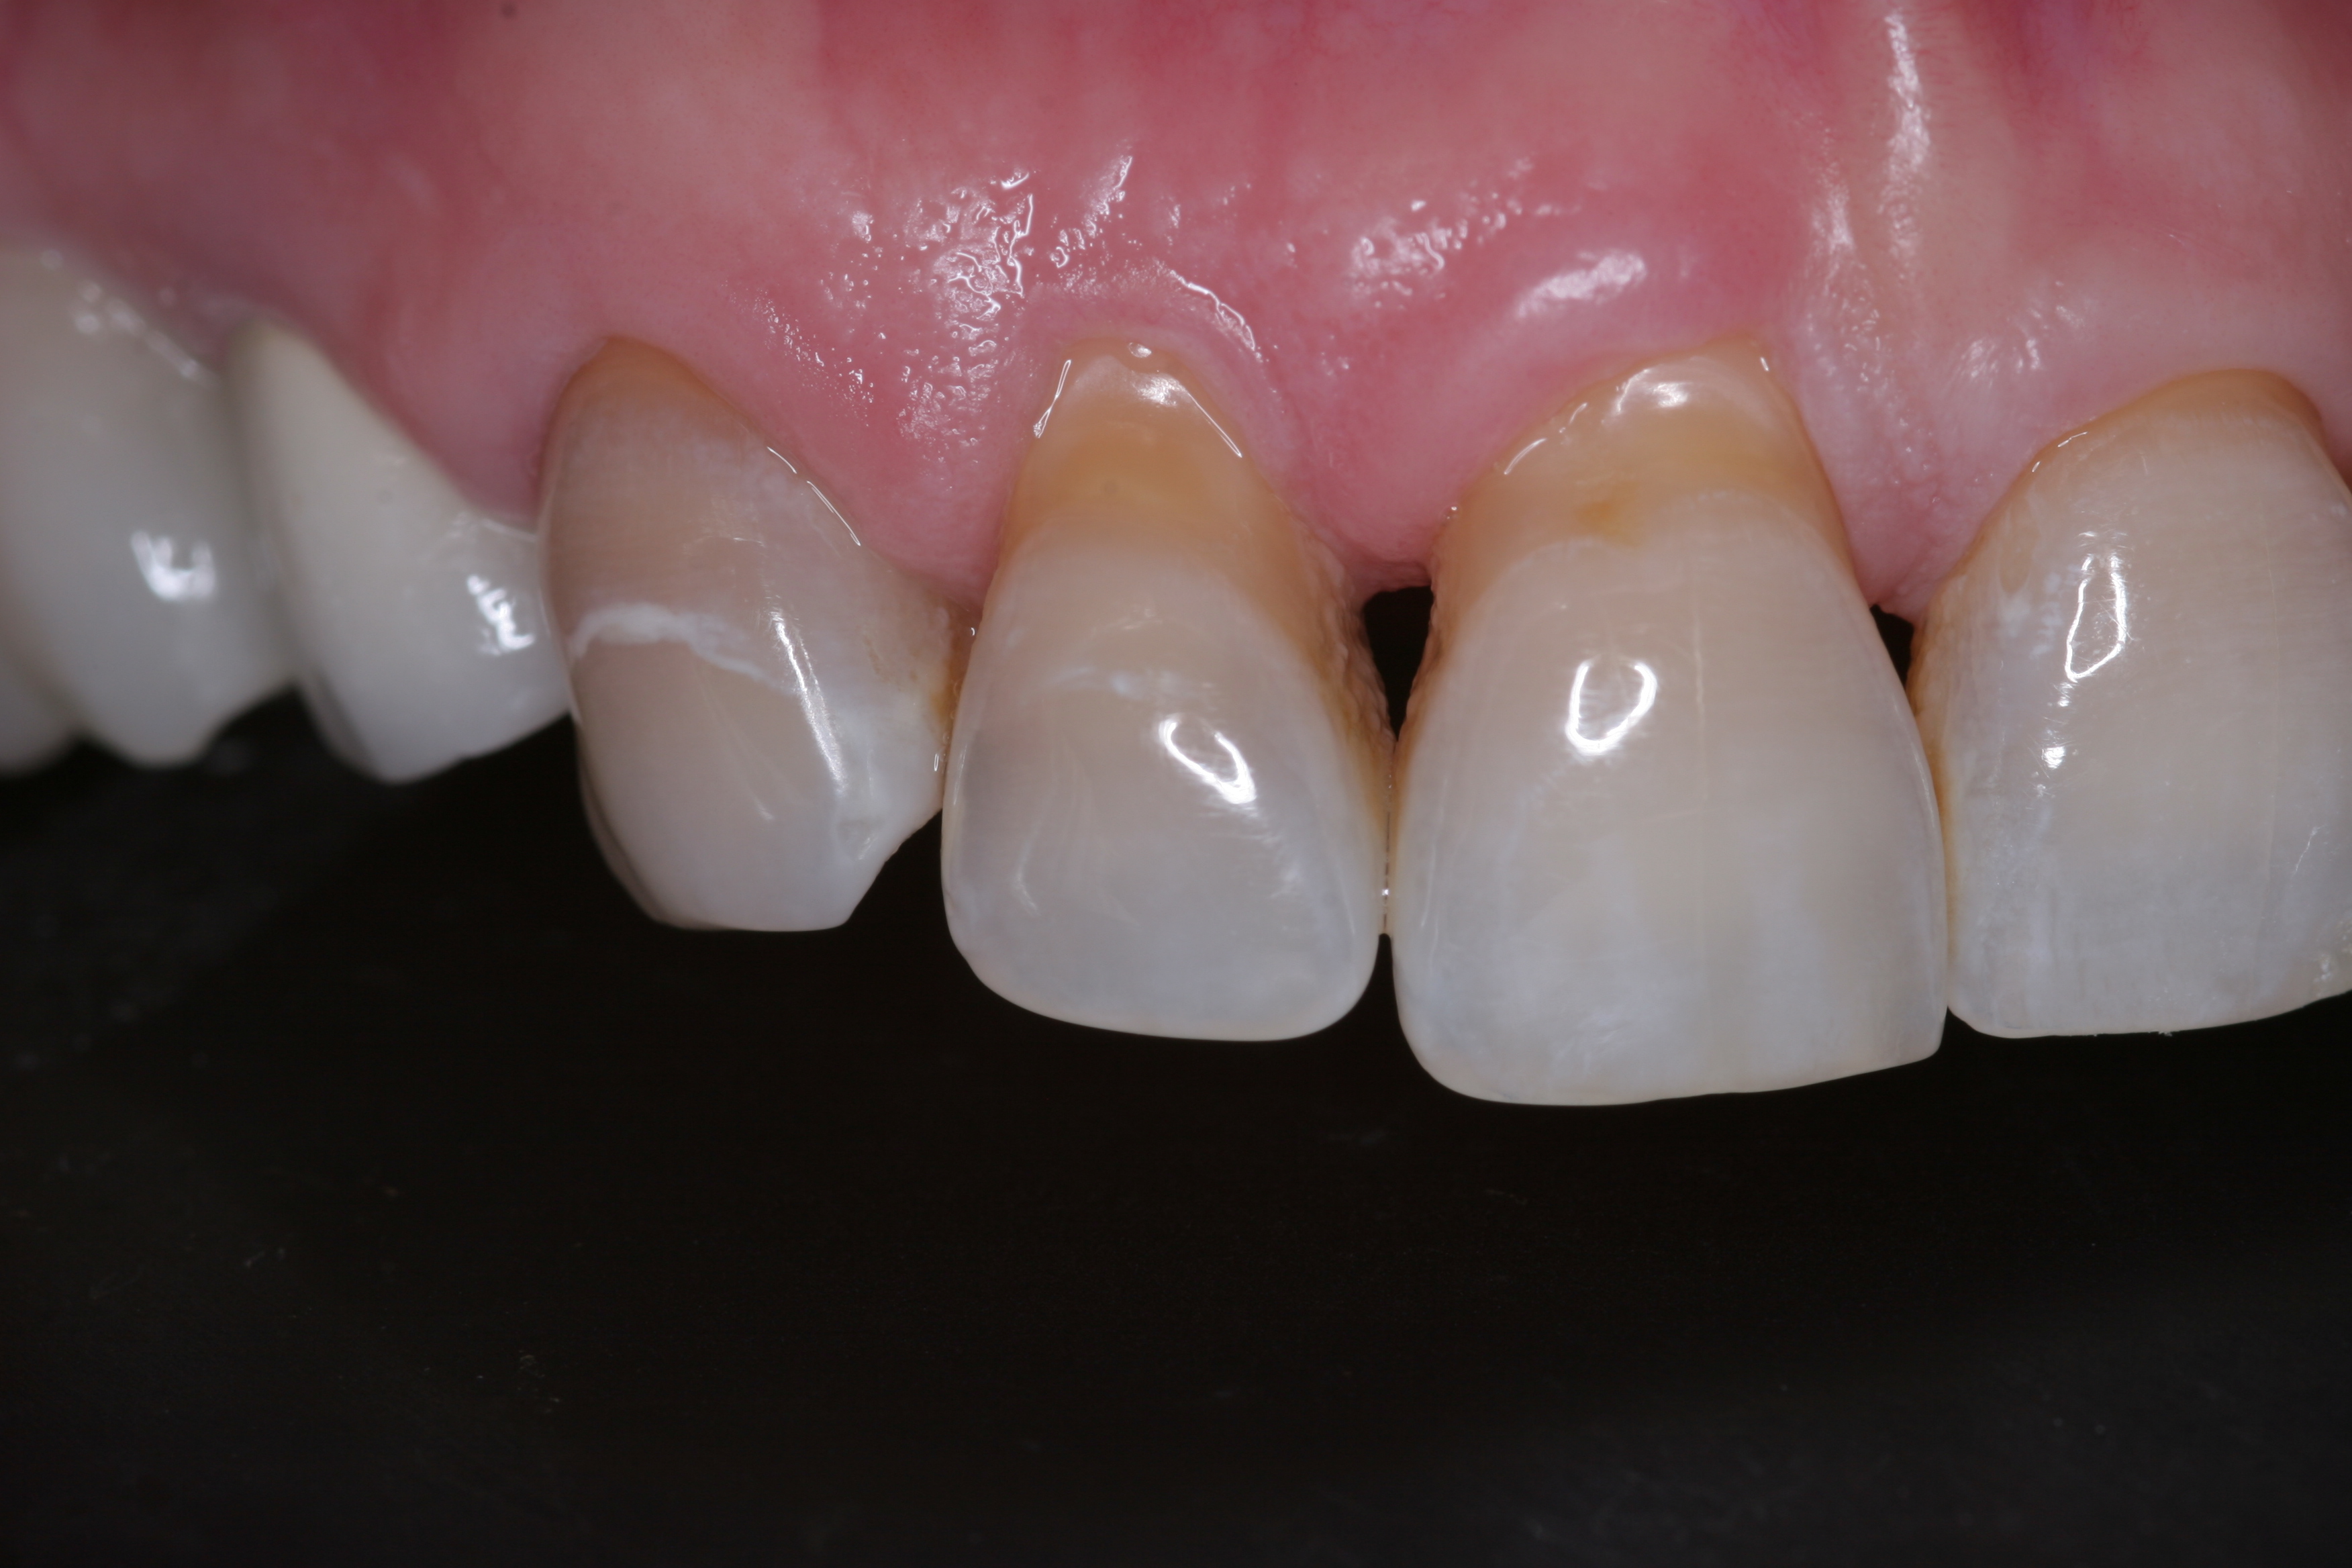

A patient presented with advanced generalized wear of her anterior teeth (Figure 10 and Figure 11). She was displeased with their overall appearance because of their color and wear (Figure 12). A complete examination was performed, revealing instability in her temporomandibular lateral poles bilaterally, sore muscles of mastication, advanced wear, a CR/MIP discrepancy, and loss of her anterior guidance due to the wear. Although the topic is beyond the scope of this article, the patient was also screened for possible sleep apnea. This included an evaluation of the Mallampati score, previous sleep therapy evaluation or treatment, snoring history, an evaluation of her neck size, her weight status, and the presence of the tonsils and their size. In every case, if this clinician suspects airway obstruction to be playing a role in tooth wear issues, the patient is referred to a sleep physician. The patient in this case displayed few apnea risk factors, and the patient’s anterior wear facets fit together like a “lock and key” pattern seen in parafunctional activity. Splint therapy was initiated to stabilize the joints and muscles. A repeatable CR position was verified through load testing. At this point diagnostic models, photographs, a CR bite record, and a facebow were taken and recorded.

(11.) A patient presented with advanced generalized wear of her anterior teeth, and was displeased with their overall appearance because of their color and wear.

Figure 11

(12.) A patient presented with advanced generalized wear of her anterior teeth, and was displeased with their overall appearance because of their color and wear.

Figure 12